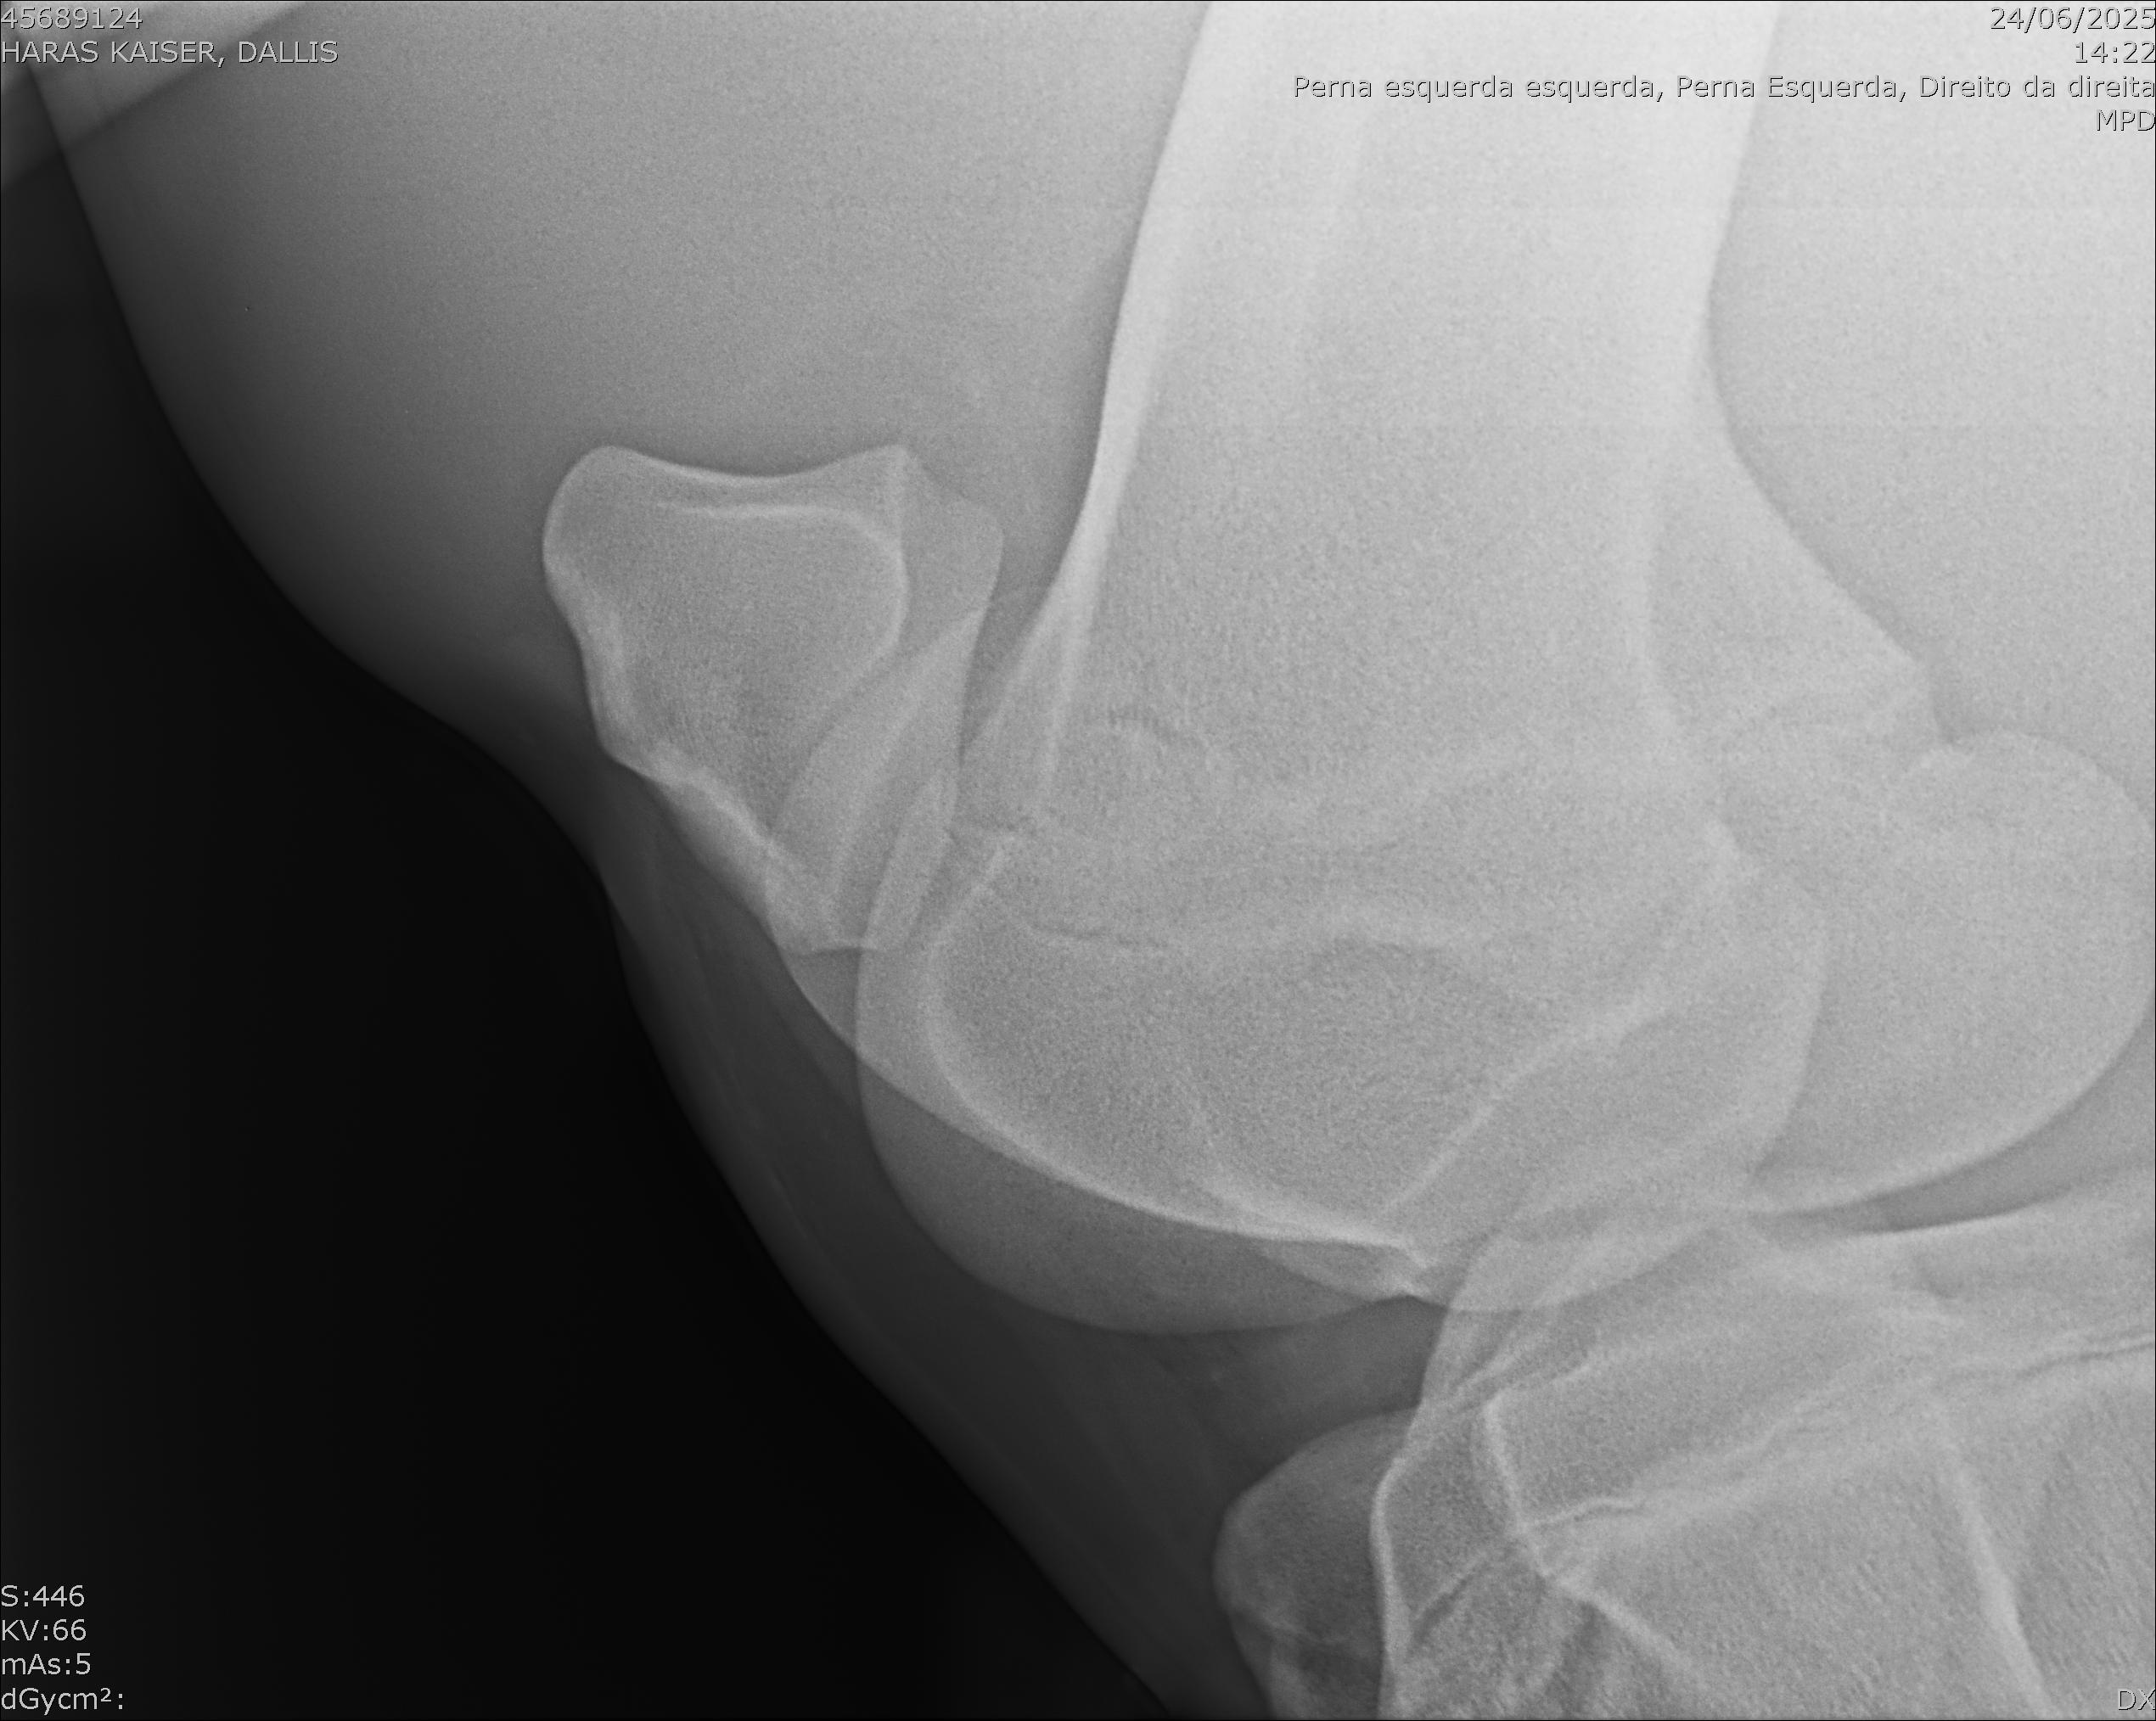

:: RAIOS-X DO LOTE